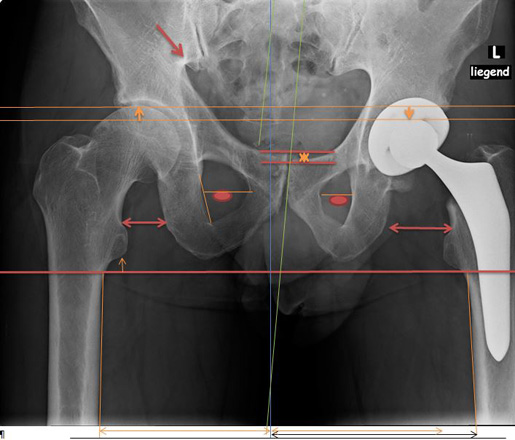

1.2

Wurde ein neues Hüftgelenk eingebaut, wegen den Schmerzen in der Leiste.

1.3

Nun sieht man, dass die Bein- und Gelenk-Stellung nicht übereinstimmt.

Die Schmerzen sind geblieben.

Abbildung Hüft / Teil Rücken / Teil Beine von hinten aufgenommen

1.5

1.6

Hüft mit Strichen Pfeilen Kreise sichtbar gemacht

Oberkörper weicht trotz Hüftgelenk Ersatz blau eingesetzte Striche aus.

Anhand der Gesässfalten wird auch der Beckentiefstand ersichtlich.

Über die Grüne Linie sieht man wie die rechte Seite geknickt wird.

Auf der linken Seite wird die Überdehnungsspannung sichtbar.

Würde die Ganz-Körper-Statik Vermessung eingesetzt, würde die Diagnose schnell und präzise die Ausweichhaltungen aufzeigen.

Würde die Ganz-Körper-Statik Vermessung bei den bildgebenden Verfahren eingesetzt, könnten Fehldiagnosen verhindert werden. Dies würde die Ursache der Skelett Ausweichhaltungen als Ursache der Muskelfehlspannungen aufzeigen.

1.7

Trotz dem wurde das andere Hüftgelenk auch noch ausgewechselt.

Trotz Operationen sind die Schmerzen geblieben.

Beachtet man das Becken und die Gelenk-Stellungen sieht man nun auf der rechten Seite eine Verdrehung des Beckenlochs.

Der Beckenspalt ist immer noch hochgezogen. Durch die Verdrehung quetscht nun die linke Seite.

Man hat die Belastung verschoben.

Bei der Statik Kontrolle wurde der Beckentiefstand und der damit verbundenen seitlichen Oberkörper- Ausweichhaltung nicht beachtet.